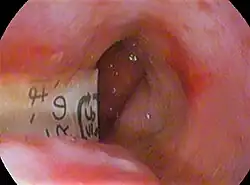

Disk batteries, also called button cells, are often mistakenly ingested, particularly by children and the elderly. They may be mistaken for a medication pill because of their size and shape, or they may be swallowed after being held in the mouth while the battery is being changed. Battery ingestion can cause medical problems including blocked airway, vomiting, irritability, persistent drooling, and rash (due to nickel metal allergy).[4]